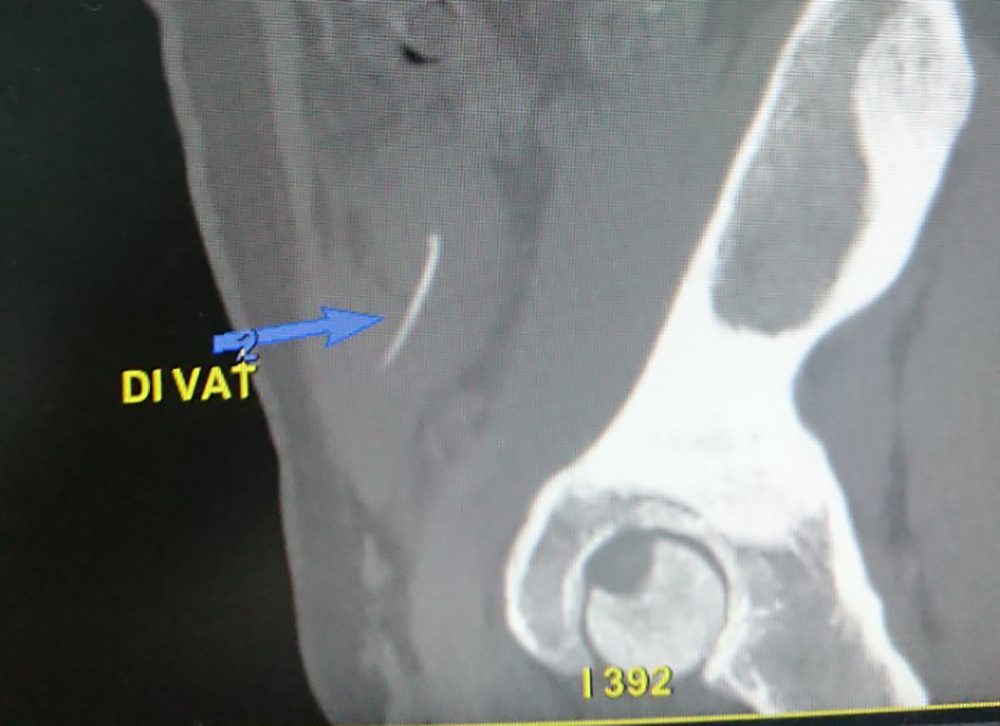

Hình ảnh dị vật là xương cá trên phim CT có cản quang

Kết quả siêu âm, chụp X-quang phát hiện có dị vật đâm thủng ruột non bệnh nhân. Các bác sĩ đã phẫu thuật nội soi, bóc tách khối viêm ở thành bụng và hố chậu. Bác sĩ phẫu tích khối viêm ở thành bụng, lấy ra một dị vật là xương cá dài 3cm…